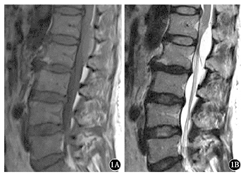

女性,49岁。主因双下肢麻木、无力7个月余入院。专科查体:腰椎活动受限,上腰段棘突压痛叩击痛,可向双下肢放射,双下肢自腹股沟以远痛觉减退,双下肢各肌肌力约为Ⅳ级,双侧膝腱反射减弱,双侧跟腱反射未引出,双下肢病理征未引出。磁共振成像(MRI)提示:腰1~2椎体水平椎管内硬膜外可见椭圆形T1W1等信号(图1A),T2W2高信号(图1B),信号均匀,边缘清楚,大小约为4.2 cm×1.3 cm,脊髓圆锥受压,椎管矢状径减小。在全身麻醉下行手术切除,术中可见肿物呈红褐色,质地软,与脊髓硬脊膜紧密粘连,小心完整地切除肿瘤组织。术后病理结果为非椎体起源海绵状血管瘤(图2)。患者术后双下肢麻木感明显减轻,自觉双下肢轻松感,术后3个月随访时,双下肢肌力基本恢复正常。

1A:均匀T1等信号;1B:均匀T2高信号